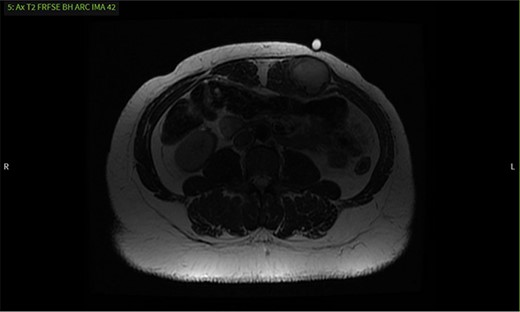

CT, ultrasound and MRI were obtained, revealing a 4.3 × 3.3 × 4.1 cm mass embedded in the left rectus muscle (Figs 1–3). Based on the MRI showing hyperintensity on T2 sequence and hypointensity on T1, we predicted the mass was a benign intramuscular myxoma. Informed consent was obtained and risks of the proposed surgical plan were explained. We proceeded with surgery to obtain a pathological diagnosis and curative resection. Under general anesthesia, the mass was resected with relatively free margins and only a small amount of underlying musculature was taken (Fig. 4). Knowledge of the abdominal wall anatomy was critical to avoid entry into the peritoneal cavity and potential compromise of its integrity. The soft tissue defect was reinforced using STRATTICE™ acellular dermal matrix mesh. Microscopic examination and immunohistochemistry diagnosed the mass as a desmoid tumor with negative margins and no evidence of malignancy (Figs 5 and 6). The patient was discharged and progressed well postoperatively.

MRI shows a mass with well-defined margins and high signal intensity on T2 sequence.

It was difficult to delineate whether the mass was primarily cystic or solid based on the initial CT, so an ultrasound was ordered. The ultrasound revealed the mass had enlarged, now measuring 5.7 × 3.6 × 4.7 cm. Internal vascularity was present, making the diagnosis of a solid mass more likely than a seroma (Fig. 2). An MRI redemonstrated the mass embedded in the left rectus muscle (Fig. 3). It had well-defined margins with high signal intensity on T2 sequence and low signal intensity on T1. On post-contrast sequences, the mass had homogeneous enhancements and a thick enhancing wall, most compatible with an intramuscular myxoma. However, without tissue biopsy, other solid tumors could not be dismissed, such as desmoid.

This is consistent with the current literature on the use of MRI as an imaging modality for desmoid tumors [1, 3]. Their presentation on MRI varies, as these tumors are thought to have early, intermediate and later stages that differ in composition [1]. In the early stage, the composition is more myxoid, with low intensity on T1 sequence and high intensity on T2, consistent with our MRI findings. At the intermediate stage, fibrous elements begin to replace the myxoid elements leading to a mixed intensity T2. Finally, in the later stage, the myxoid background is completely replaced with fibrous elements leading to low intensity on both T1 and T2. Our patient likely presented in an earlier stage and therefore had features most similar to that of a benign myxoma as opposed to a later stage desmoid tumor.